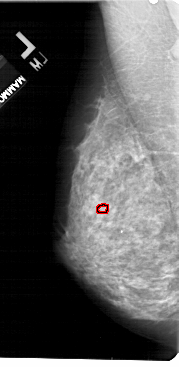

FILE: A_1755_1.LEFT_CC.OVERLAY

TOTAL_ABNORMALITIES 1

ABNORMALITY 1

LESION_TYPE CALCIFICATION TYPE PLEOMORPHIC DISTRIBUTION CLUSTERED

ASSESSMENT 4

SUBTLETY 1

PATHOLOGY BENIGN

TOTAL_OUTLINES 1

LEFT_CC LINES 5236 PIXELS_PER_LINE 2506 BITS_PER_PIXEL 12 RESOLUTION 43.5 OVERLAY